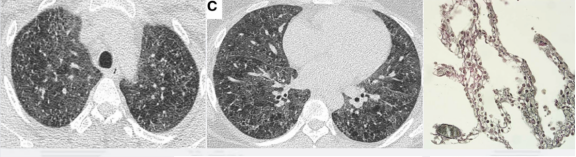

图:(从左至右)急性、亚急性、慢性

1、所谓急性HP,就是患者接触了较高水平的暴露,例如有患者喜欢饲养鸟类,尤其喜欢宠物鸽子,于是到交易市场去看,在这个过程中,可能出现了间断高水平暴露,于是一些易感个体就在很短的时间内(4到12小时)出现了流感样症状和呼吸道症状,而肺内则出现了一些磨玻璃影。

2、也有一些患者急性发作伴发热,劳力性呼吸困难、乏力和咳嗽,影像表现为小叶中央性的弥漫性的腺泡结节,称之为亚急性HP

3、还有些患者持续性低水平暴露,起病很隐匿,当我们发现时,已经出现了劳力性呼吸困难,干咳,体重减轻和乏力,而影像出现了既有磨玻璃影,也有肺纤维化的表现,称之为慢性HP